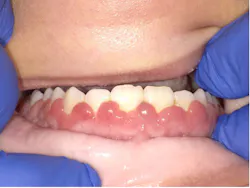

In two weeks, the patient returned for a follow-up appointment. The tissue had grown back almost to the original levels (figures 4 and 5). Note the intense red color of the maxillary gingivae.